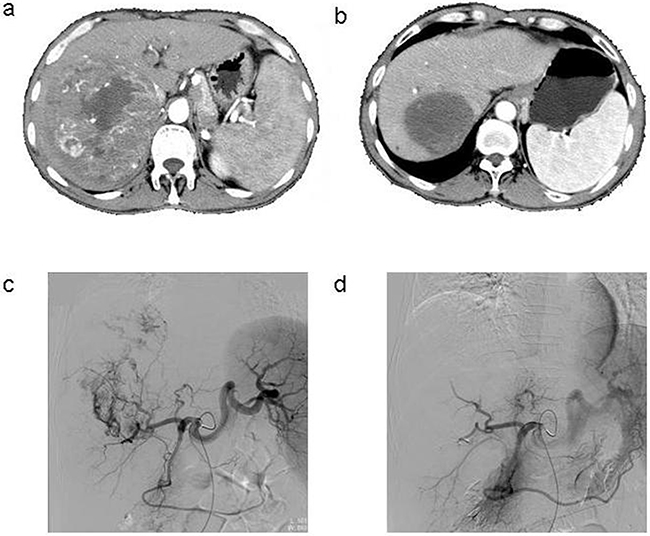

The tumor response was evaluated using CT/MRI according to the mRECIST criteria [7]. Following the HepaSphere microsphere treatment, two patients (6.7%) had complete responses (CR) (Figure 1), 17 (56.7%) had partial responses (PR) (Figure 2), seven (23.3%) had stable disease (SD), and four (13.3%) had progressive disease (PD). The total objective response was 63.3%, and the disease control rate was 86.7%. The pre-TACE and post-TACE tumor indicator details are given in Table 1, and many of the tumor markers had decreased one month postembolization.

Figure 1: a. Contrast-enhanced CT scan done before the procedure in the patient with HCC, b. Enhanced CT showed complete tumor necrosis 6 months after three TACE sessions, c. Common artery angiography of the patient with HCC during 1st TACE, selective catheterisation of the pathologic branch of right hepatic artery supplying the tumor, d. After chemoembolization angiography with 1st TACE.